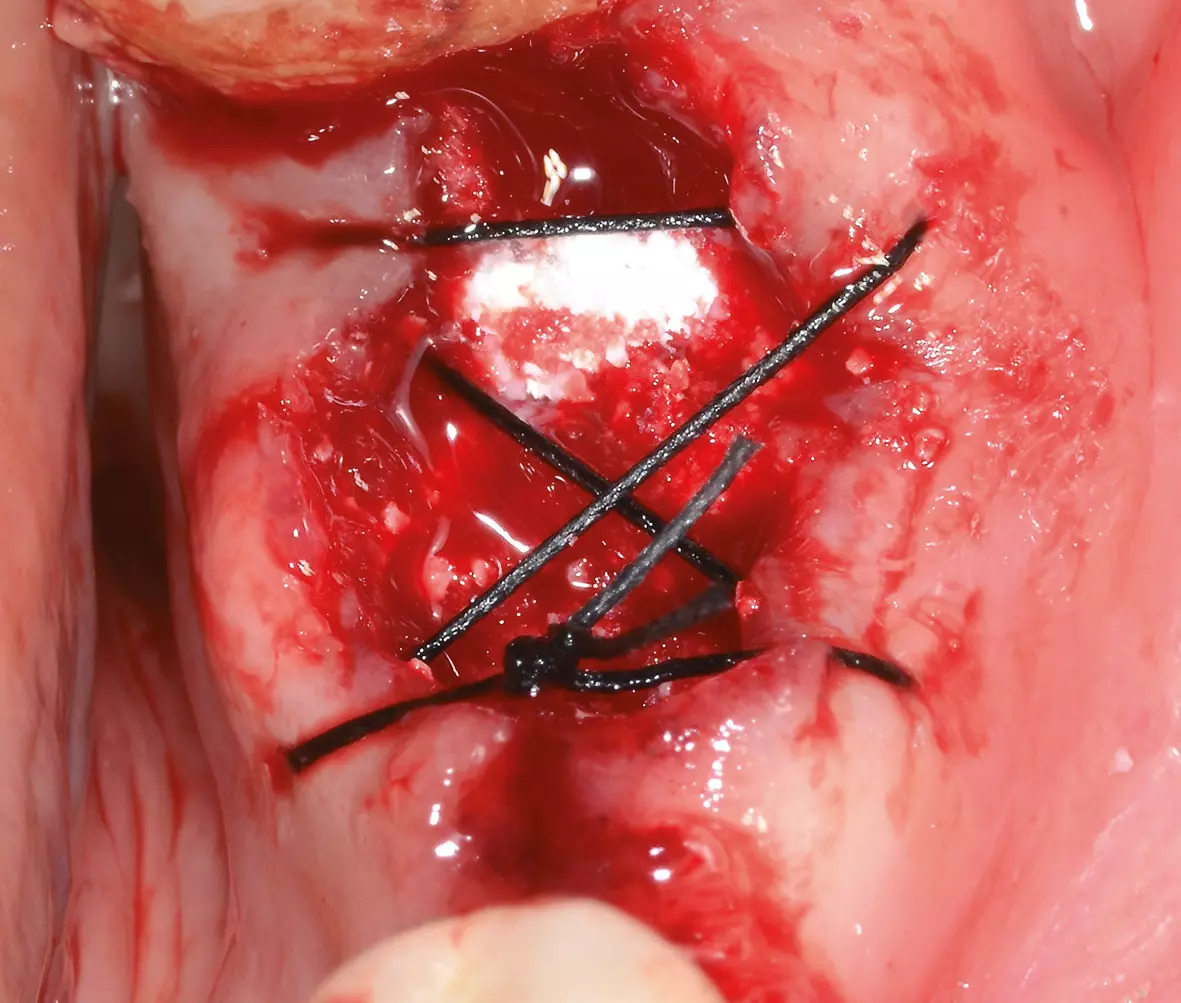

Um einer Resorption des Knochens um die Extraktionsalveole vorzubeugen, wurde die Alveole mit einem intraoperativ individualisiertem bovinen Block DBBM-C (Deproteinized bovine bone Matrix-Collagen, Geistlich BioOss-Collagen, Geistlich Biomaterials) aufgefüllt. Im Anschluss erfolgte eine Adaptionsnaht (Abb. 2). Die postoperative Phase verlief ohne Besonderheiten, sodass die Nähte nach sieben Tagen entfernt werden konnten. Beim Kontrolltermin nach acht Wochen zeigte sich die Wunde vollständig und reizlos abgeheilt (Abb. 3).